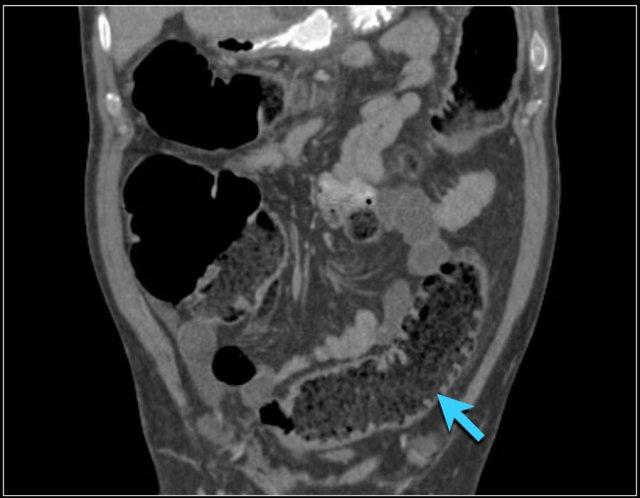

Các hình ảnh này thuộc về bệnh nhân bị tắc ruột non dạng quai kín.

Lưu ý nhóm các quai ruột non có thành dày ở vùng bụng trên phải (mũi tên vàng).

Phù nề mạc treo ruột (mũi tên đỏ) cho thấy tình trạng tăng áp lực tĩnh mạch do thắt nghẹt.

Giãn mạch máu

Tăng áp lực tĩnh mạch trong thắt nghẹt cũng dẫn đến giãn tĩnh mạch (mũi tên vàng).

Bệnh nhân này cũng có tắc ruột dạng quai kín với kiểu ngấm thuốc xám của các quai ruột bị thắt nghẹt (mũi tên đỏ).

Lưu ý sự ngấm thuốc bình thường của ruột non ở phía trên vị trí tắc nghẽn (mũi tên xanh lá).